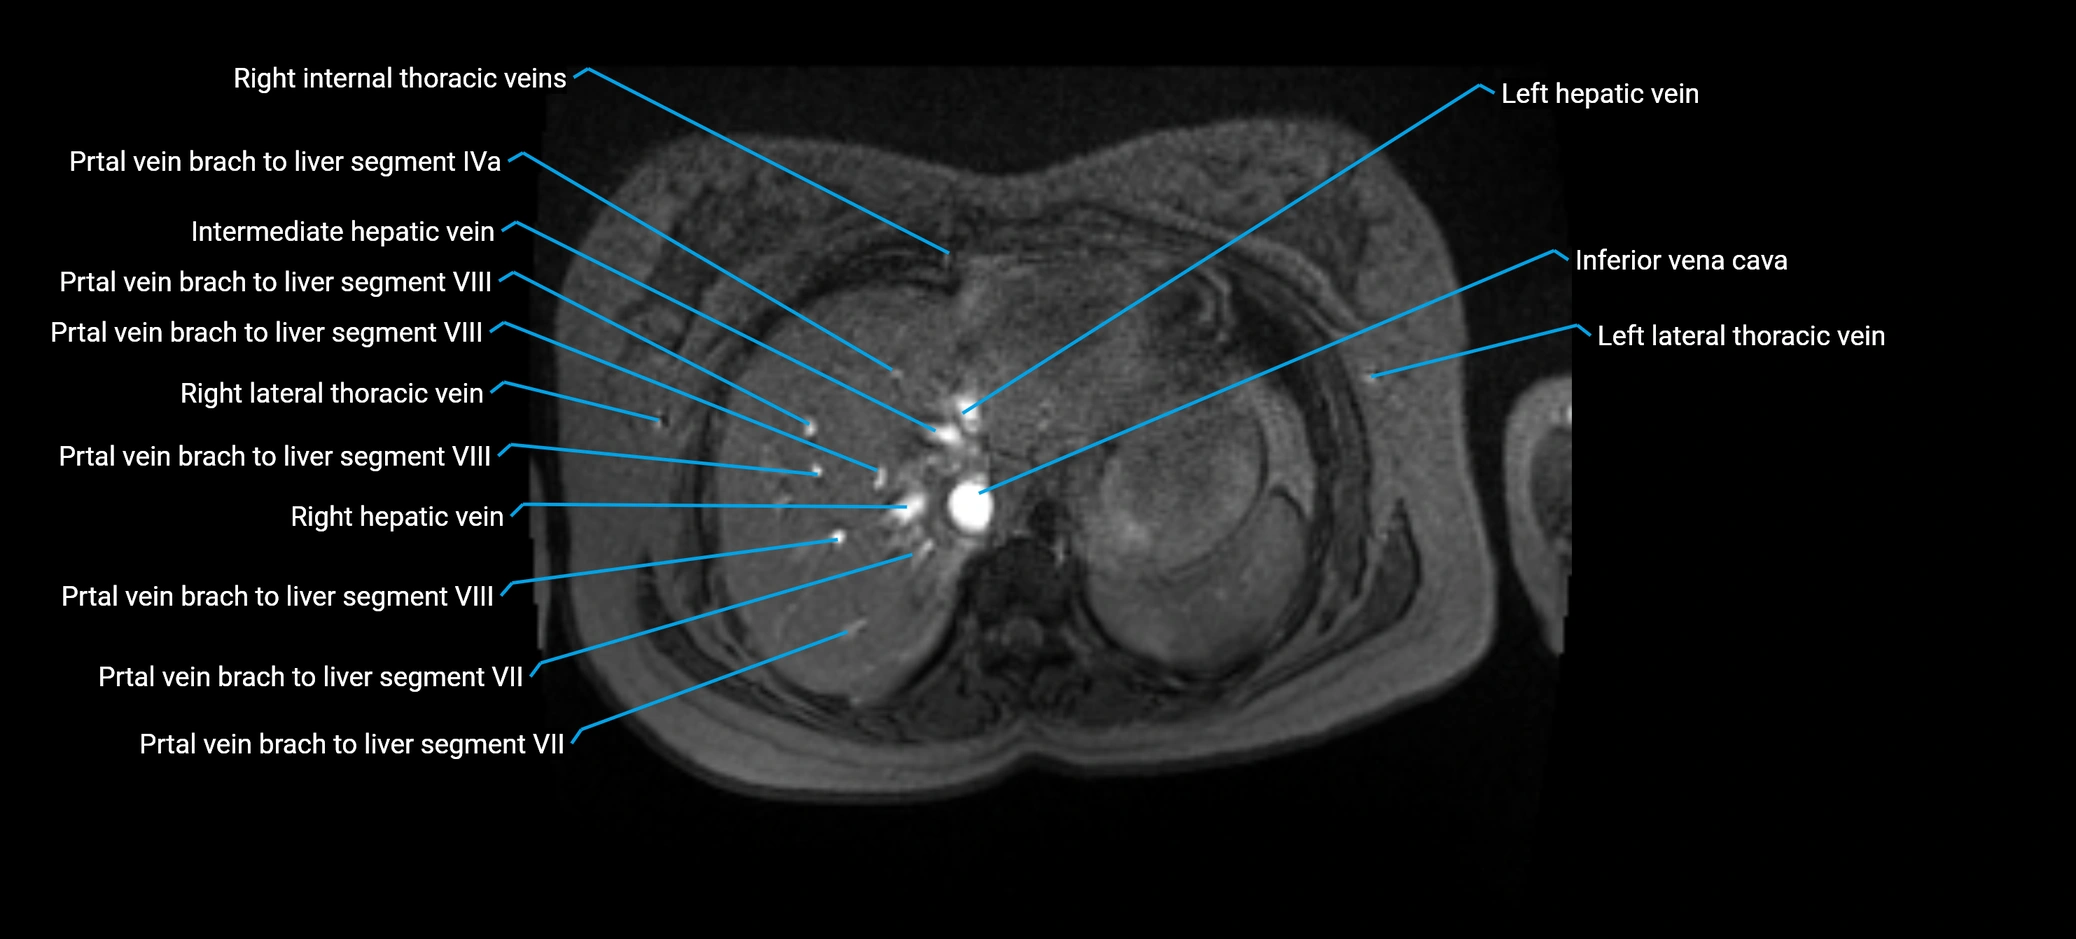

MRI image

image